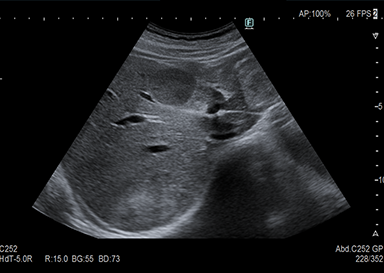

超音波検査とは

頸部(動静脈・甲状腺)、心臓、腹部(肝臓・胆のう・膵臓・脾臓・腎臓・膀胱・腹部大動脈等)、下肢(動脈・静脈)等が観察できる検査です。

高齢者でも無理なく行えます。病変の経過観察、早期発見としたスクリーニング検査などが行えます。